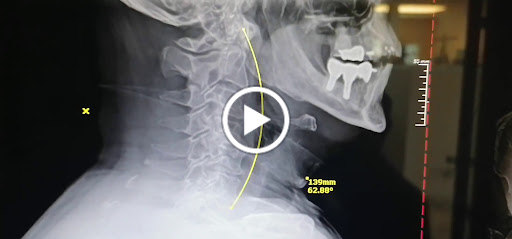

Ive been going to Dr. Foss for about 3 weeks now, and within the first week I had a great deal of relief and my back has continued to improve. He scheduled X-rays, and walked me through the issues apparent on the X-rays in a very clear and concise manner. I highly recommend him, as hes excellent and has very reasonable pricing for his services.